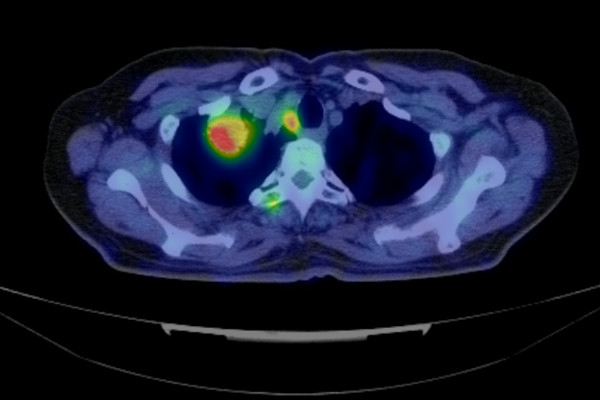

原発不明がんの多くはCTやMRIなどの画像診断を行ったとき、原発部位候補が複数ある、あるいは転移と思われる病巣しか見つからないので、原発部位が決められなかった腫瘍です。しかし、過去の検査画像とあわせて検討したり、PET/CTで全身をチェックしたりすることで原発部位を推定することが出来ます。推定が難しい場合でも原発候補を絞って有効な治療法を検討することに役立ちます。

下の写真は原発不明がんの診断時に放射線診断科医がみている実際のPET/CTの画像です。

赤い部分が腫瘍です